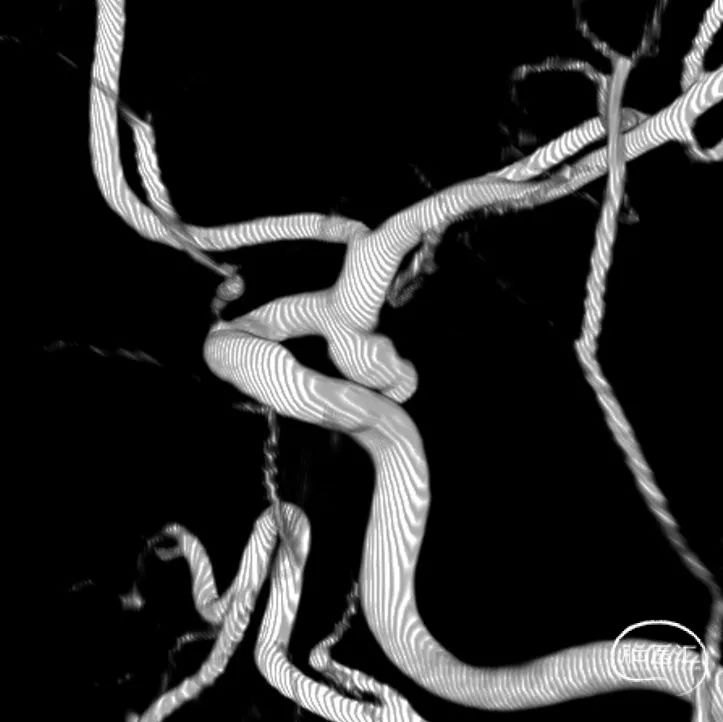

➢术前3D重建

➢术前3D测量

动脉瘤瘤颈口:2.79mm

动脉瘤:3.76mm * 4.61mm

动脉瘤子囊:2.79mm*1.99mm